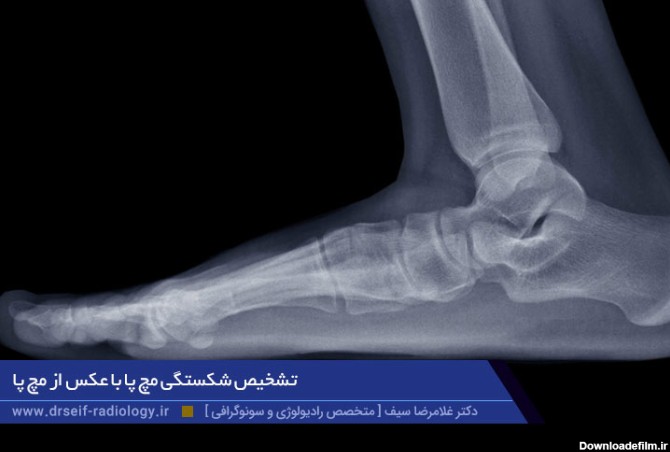

برای درمان شکستگی مچ پا ابتدا باید تشخیص به درستی صورت بگیرد. مهم ترین ابزار برای تشخیص این نوع شکستگی بررسی تصاویر رادیوگرافی است.

شکستگی مچ پا یکی از ممکن است به دلایل مختلف برای هر کسی رخ بدهد، در ادامه سعی داریم به بررسی دلایل و درمان و مدت زمان درمان شکستگی مچ پا بپردازیم.